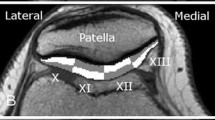

T2values were compared in six different regions in the femoral (anterior AFC, mid MFC, posterior PFC) and tibial (anterior ATC, mid MTC, posterior PTC) cartilage (Fig. 1). Each ROI was further subdivided into equally thick superficial and deep layers. The ROIs were selected in the JiveX DICOM Viewer (JiveX 4.3; VISUS Technology Transfer GmbH, Bochum, Germany) by a radiologist (N.N.) with 16 years of experience. To assess inter-observer variability, another two observers (N.N. 10 years of experience, N.N., 15 years of experience), blinded to previous results, evaluated five volunteers and five patients, and the coefficient of variation was calculated.